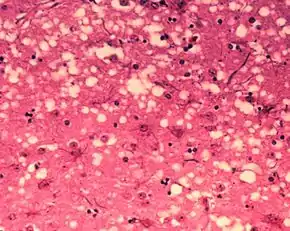

Brain tissue of a cow with BSE showing the typical microscopic "holes" in the grey matter

Diagnosis of BSE continues to be a practical problem. It has an incubation period of months to years, during which no signs are noticed, though the pathway of converting the normal brain prion protein (PrP) into the toxic, disease-related PrPSc form has started. At present, no way is known to detect PrPSc reliably except by examining post mortem brain tissue using neuropathological and immunohistochemical methods. Accumulation of the abnormally folded PrPSc form of PrP is a characteristic of the disease, but it is present at very low levels in easily accessible body fluids such as blood or urine. Researchers have tried to develop methods to measure PrPSc, but no methods for use in materials such as blood have been accepted fully.

The traditional method of diagnosis relies on histopathological examination of the medulla oblongata of the brain, and other tissues, post mortem. Immunohistochemistry can be used to demonstrate prion protein accumulation.[25]